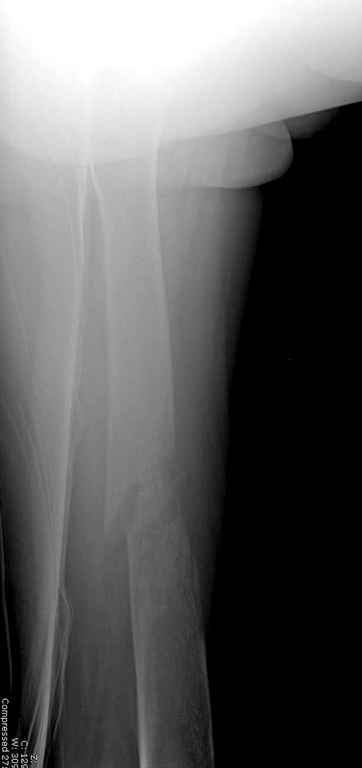

Здесь случай 66 летней пациентки со спонтанными болями в левой нижней конечности, обратилась в приемное, сделаны снимки бедра и КТ.

Патологический перелом бедра, конечность на вытяжении.

Да, я с достаточной для принятия решения степенью уверенности могу говорить, что это метастаз, потому что

-это не характерный возраст для осеосаркомы

-это не типичная локализация для остеосаркомы

-это не характерная рентгенкартина для остеосаркомы